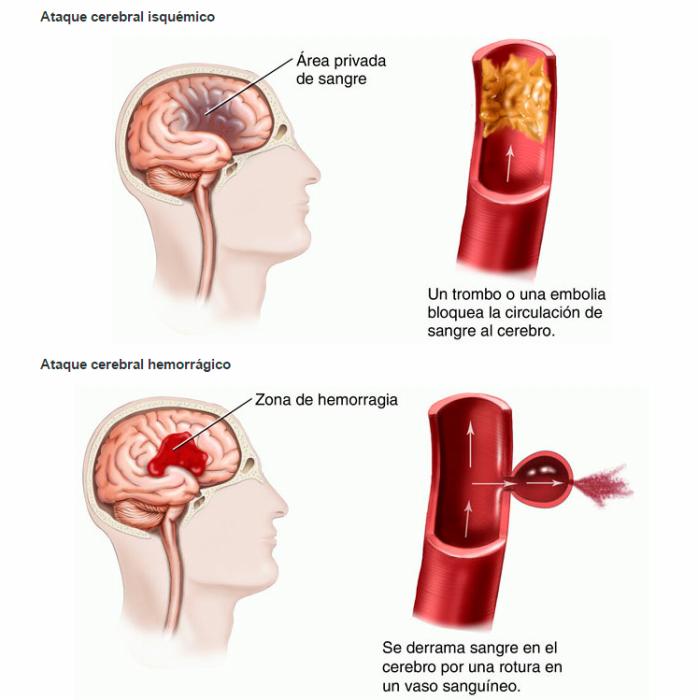

“El ataque cerebral designa a una enfermedad de la cual se altera súbitamente el flujo de sangre en el cerebro. Hay dos tipos principales de ACV: los infartos cerebrales (isquemia), dónde el problema es que el ‘caño se tapa’, y parte del tejido cerebral queda sin su aporte sanguíneo porque un coágulo tapona el vaso. O bien las hemorragias cerebrales, donde ‘el caño se rompe’ y el contenido, o sea la sangre, inunda el tejido”, explicó el médico neurólogo Javier Moschini a ‘Río Negro’.

Cualquiera de las dos situaciones puede provocar que las neuronas se debiliten o mueran, ya que sin oxígeno las células nerviosas no pueden funcionar. Las partes del cuerpo controladas por las regiones del cerebro afectadas, consecuentemente, también dejan de funcionar. Los efectos de un ataque cerebral son a menudo permanentes, ya que las células cerebrales muertas no se pueden reemplazar.

El 80% de los episodios de ACV son infartos. El 20% restante corresponde a casos de hemorragias.